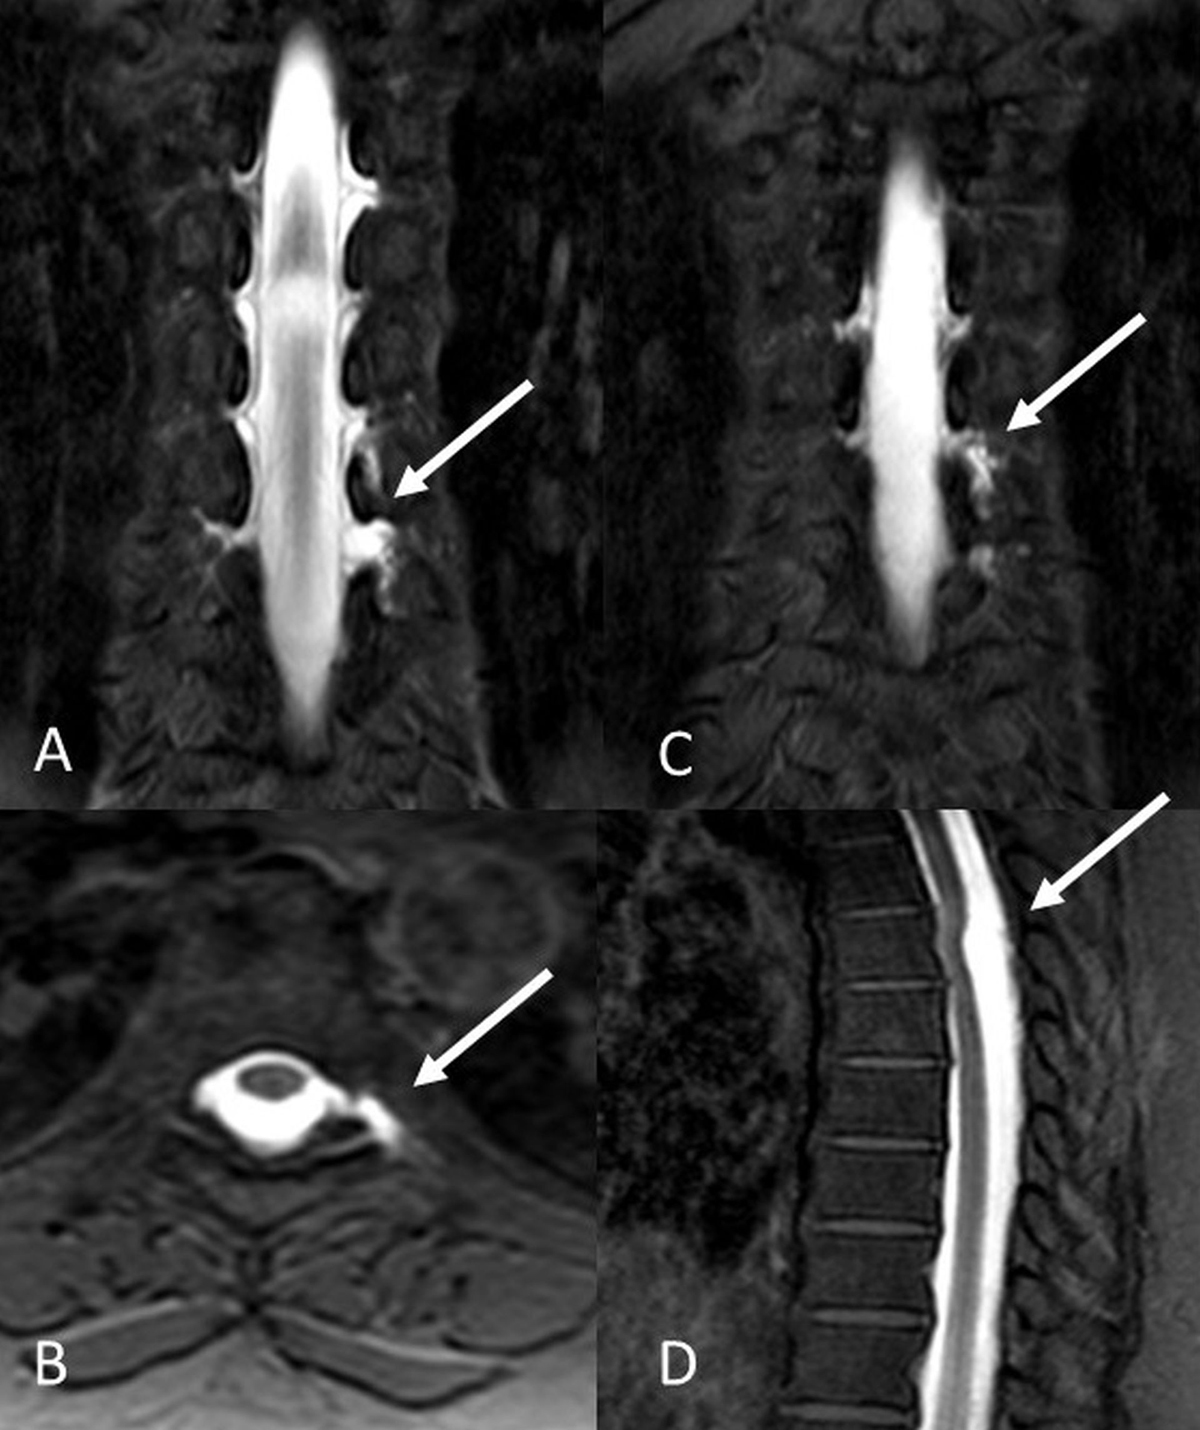

Figure 2

Intrathecal Gd-MRM images in a 47-year-old female patient demonstrated CSF leak at T6–T8 levels. T1W-SPIR coronal (A, B), and axial (C) images revealed diverticular pouching and CSF leakage. A cystic lesion posterior to spinal cord was revealed in T1W-SPIR sagittal images (D).